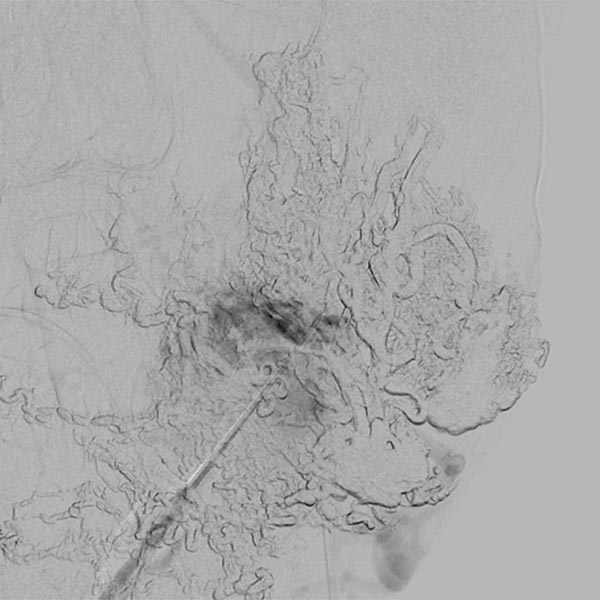

Direkte perkutane Punktion des Nidus mit einer Nadel und Durchführung einer DSA. Damit Kontrolle der korrekten Lage der Nadelspitze vor Embolisation mittels Ethylen-Vinyl Alkohol-Kopolymer in Direktpunktionstechnik.

Erneute Direktpunktion des Nidus und DSA zur Überprüfung der Nadellage.

Langsames, direktes Auffüllen des Nidus und der abführenden Venen mittels Ethylen-Vinyl Alkohol-Kopolymer (EVOH) in Roadmap-Technik. Bereits vorinjeziertes EVOH wird in dieser Technik wegsubtrahiert und ist nur in Umrissen erkennbar.

Auffüllung des gesamten Nidus der AVM mittels Ethylen-Vinyl Alkohol-Kopolymer, das in dem hier dargestellten Röntgenbild (a.-p.) als schwarzer, netzartiger röntgendichter Ausguss (sogenannter Cast) innerhalb der verschlossenen AVM-Gefäße sichtbar wird.

Auffüllung des gesamten Nidus der AVM mittels Ethylen-Vinyl-Alkohol-Kopolymer, das in dem hier dargestellten Röntgenbild (seitliche Ansicht) als schwarzer, netzartiger röntgendichter Ausguss (sogenannter Cast) innerhalb der verschlossenen AVM-Gefäße sichtbar wird.